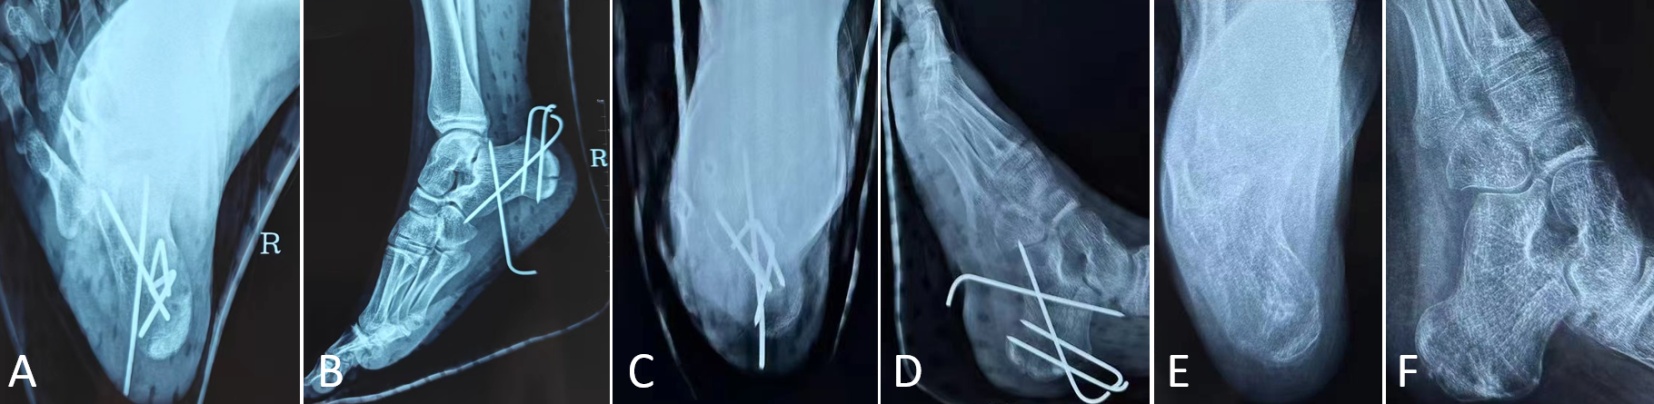

术后复查及随访:术后第一天复查X线片显示骨折复位满意,内固定位置良好(图2(A)图2(B));出院后嘱患儿适当锻炼,维持支具固定,避免剧烈活动,以免造成再次骨折。术后6周复查X线片提示骨折断端骨痂生长满意(图2(C)图2(D)),达到临床愈合,予以拔除钢针内固定;术后8周复查X线提示骨折愈合良好,有连续性骨痂形成,骨折线模糊,关节活动度评估显示:踝关节背屈达到15˚,跖屈45˚,距下关节活动度恢复至正常范围的80%。AOFAS评分从术后4周的75分提升至术后8周的82分,表明功能恢复呈现持续改善趋势(图2(E)图2(F))。随访过程中均未出现感染及其他异常情况。通过标准化的AOFAS评分系统,我们能够更加客观、量化地评估手术疗效,为临床决策提供可靠依据。

((A)和(B)):术后第一天跟骨轴位、侧位片;((C)和(D)):术后6周跟骨轴位、侧位片,提示骨折断端骨痂生长满意,达到临床愈合,予以拔除内固定钢针;((E)和(F)):术后8周跟骨轴位、侧位片,提示骨折断端愈合良好,骨折线模糊,骨折愈合良好,关节活动良好。

Figure 2. Postoperative review and follow-up

2. 患者术后复查及随访